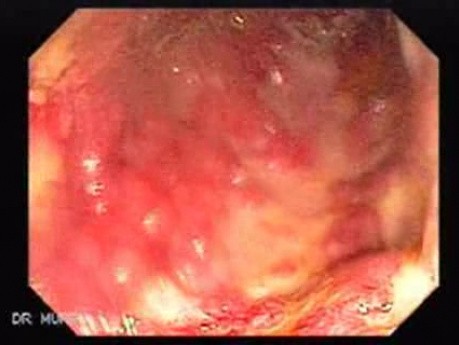

Mnogie wrzody odbytnicy (14 z 110)

20 do 25% pacjentów z rozległym wrzodziejącym zapaleniem jelita grubego ostatecznie przechodzi kolektomię, zwykle dlatego, że ich choroba nie zareagowała na leczenie farmakologiczne. W wrzodziejącym zapaleniu...

Ostre rozdęcie okrężnicy nakładające się na rzekomobłoniaste...

Ze względu na niekontrolowany i masywny krwotok pacjent przeszedł kolektomię. Widoczny fragment usuniętego jelita grubego.